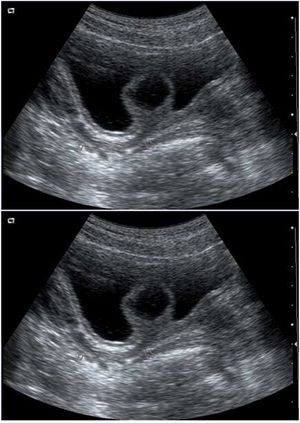

Case History: A 57-year-old woman presented complaining of a long lasting epigastric pain. The pain was irregular, vague without spreading or progression or correlation to alimentary habit.